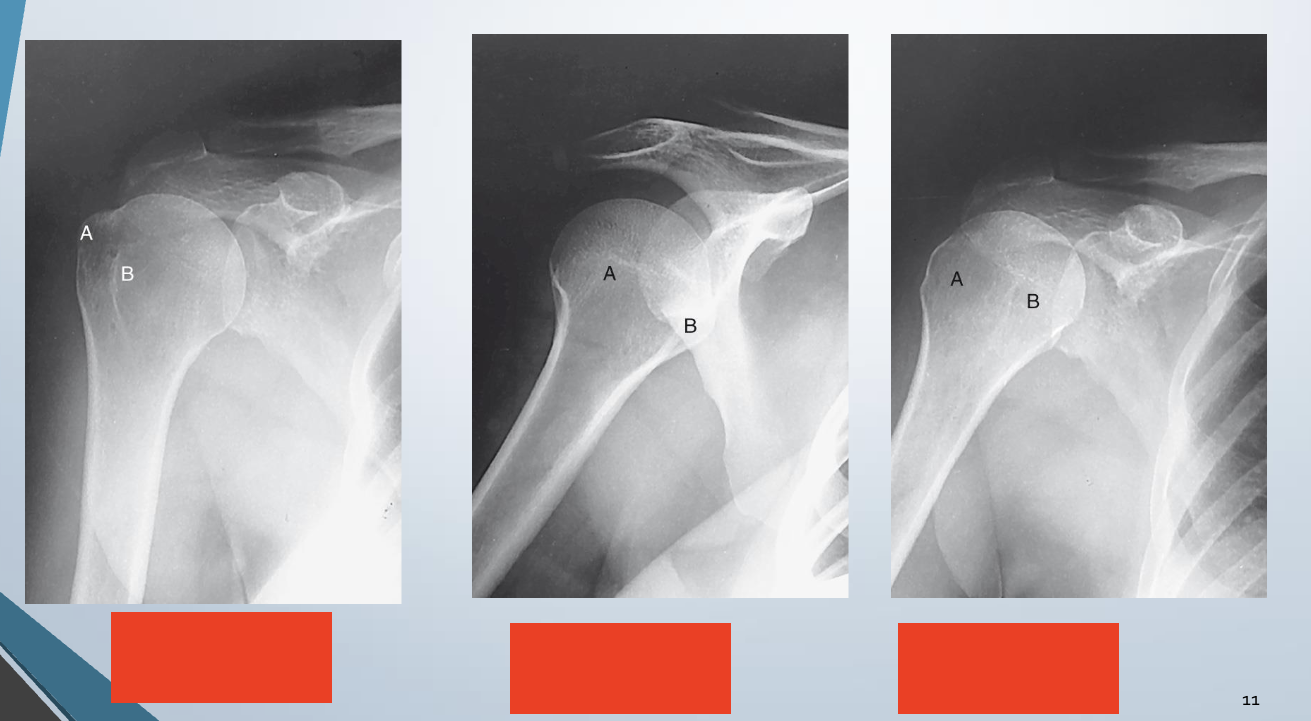

Neutral, External, Internal

1 - External

2 - Internal

3 - Neutral

Shoulder AP external rotation

Epicondyles parallel to IR

CR- 1 inch inferior to coracoid process

Same position as AP humerus

Greater tubercule in profile laterally, lesser tubercule superimposed head of humerus

Scapulohumeral joint centered

Proximal humerus, upper scapula, clavicle visualized

AP shoulder Internal rotation

Epicondyles perpendicular to IR

CR - 1 inch inferior to coracoid process

Looks like lateral humerus

Lesser tubercule in profile medially, greater tubercule superimposed over head

Proximal humerus, upper scapula, and clavicle visualized